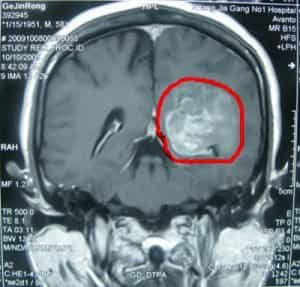

تم إدخال المريض جينغونغ غي، وهو مريض ذكر يبلغ من العمر 59 عامًا من الصين، إلى مستشفى بكين بوهوا الدولي (BPIH) في الصين في 20 أكتوبر 2009، مصابًا بورم سحائي غير نمطي في منطقة مثلثة.

قبل ستة عشر شهرًا من دخوله المستشفى بسبب ورم سحائي غير نمطي في المنطقة المثلثية اليسرى، بدأ السيد جي يشعر بضعف في مرونة ساقه اليمنى، وكأنه يعاني من ضعف في حركتها. لم يسعَ للعلاج فورًا. مرت ستة أشهر، وتفاقمت الأعراض تدريجيًا، مما أثر على مشيته، وكان لصعوبة تحريك ساقه اليمنى أثر سلبي واضح على حياته. ذهب إلى مستشفى محلي وأجرى تصويرًا بالرنين المغناطيسي للدماغ، والذي أظهر وجود ورم في المنطقة المثلثية من البطين الجانبي الأيسر. نُصِحَ بالتدخل الجراحي. رغبةً منه في الخضوع لجراحة الأعصاب لعلاج هذا الورم السحائي غير النمطي، تم إدخال المريض جينرونغ جي إلى مستشفى بكين الدولي للأمراض النفسية.

فحص بالأشعة قبل الجراحة